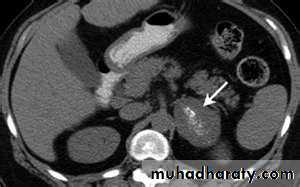

2- imaging study for the localization of the phaeochromocytoma and/or metastases. MRI is preferred because contrast media used for CT scans can provoke paroxysms.

3-MRI and CT are equally effective in distinguishing adrenocortical adenoma from carcinoma .